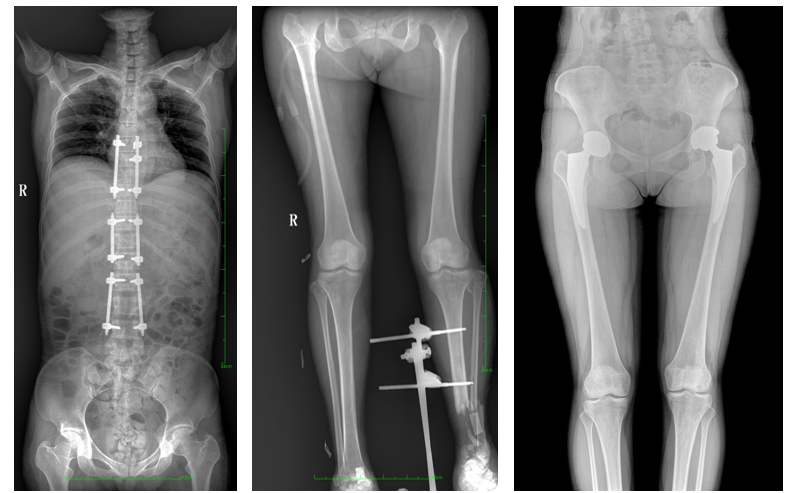

17"*34"有效视野,是市面大尺寸平板的2倍,一次成像不拼接。相较于多张摄影再软件拼接的DR设备,PLX8600解决了拼接图像存在密度不均匀,拼接处图像配准和放大效应等问题,给临床带来了真正的大视野影像解决方案,高清画质,准确成像不失真,可一次性覆盖全脊柱或双下肢影像。PLX8600大视野平板动态DR摄影速度快,患者可以更快的完成检查,且单次摄影辐射剂量是常规多张摄影再软件拼接DR的1/2或1/3,低剂量给患者更多关爱。

除常规静态摄影外,PLX8600大平板具备动态透视和点片功能,透视采集功能可支持大视野、多角度的可视化观察。通过可视化的动态影像,配合点片功能,能够很好的观察复杂部位病灶,有效的抓取关键帧,降低患者多次摄片的概率,安全又高效。如:全脊柱状态评估、长骨关节活动度、下肢静脉造影瓣膜功能评估、消化道功能评估、脊髓造影等更多大视野临床应用,多面手给医生更多惊喜。